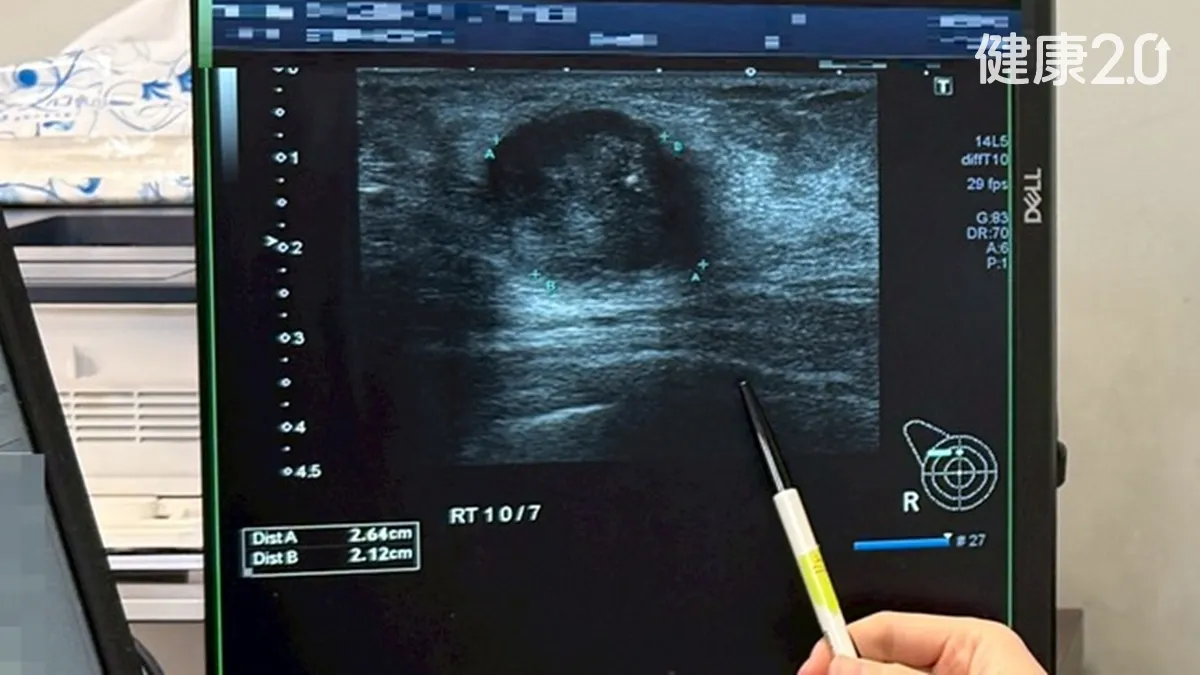

女性意外摸到硬塊竟是三陰性乳癌 新藥基金救 glyphicon性命